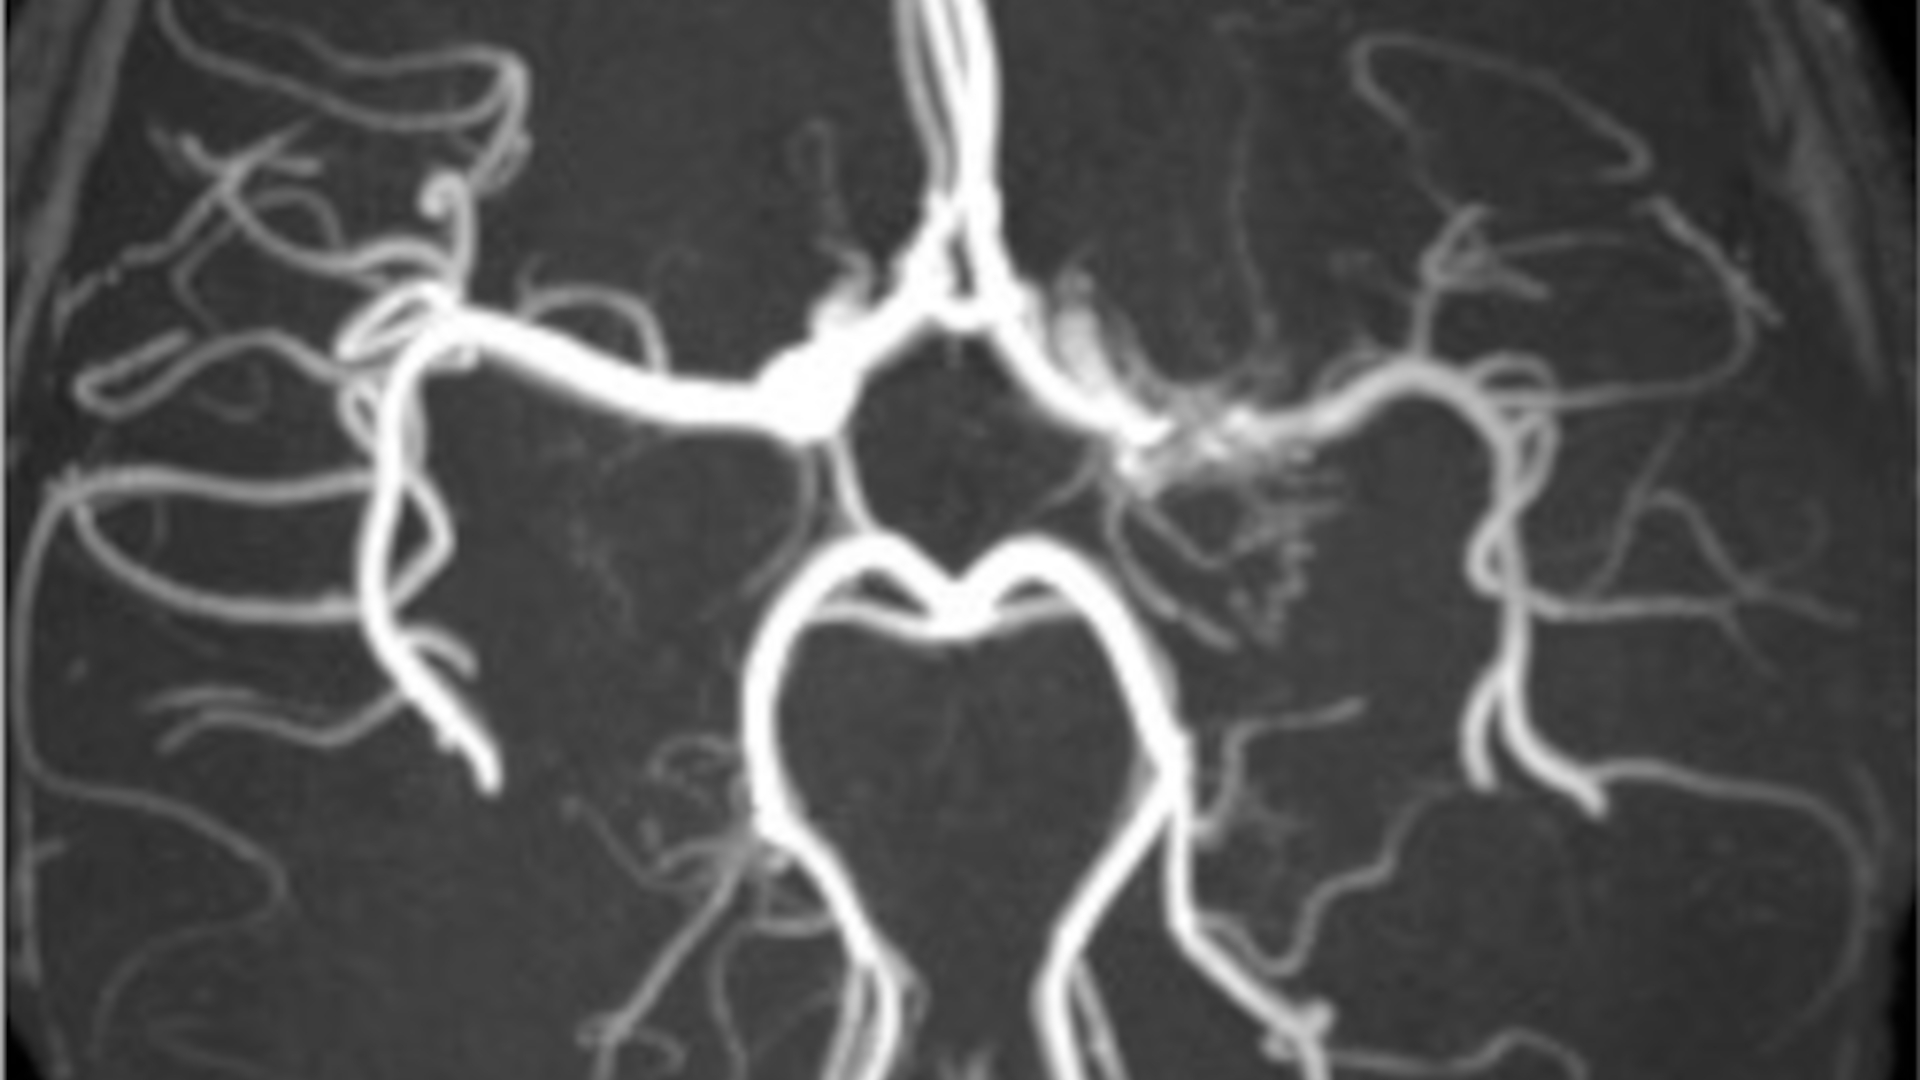

Science Ouverte Parution : L’impression 3D en chirurgie orthognathique, à lire en libre accès La fabrication additive permet de produire des dispositifs médicaux spécifiques aux patients, contribuant à offrir des soins sur mesure.... Lire la suite Enseigner, apprendre, former à l’informatique à l’école : regards croisés Le projet « Informatique à l’école : conceptualisations, accompagnement, ressources » IE CARE, financé par l’Agence... Lire la suite À lire dans Emerging Neurologist : maladie de Moya Moya, deux cas étudiés au CHU de Rennes Depuis les années 2000, plusieurs anomalies de l’artère cérébrale moyenne ont été décrites dont le twig-like, ou maladie de Moya Moya.... Lire la suite Actualités Parution : L’impression 3D en chirurgie orthognathique, à lire en libre accès| Publications Retour sur la journée « Construire l’accompagnement à la gestion des données de la recherche »| données de recherche Enseigner, apprendre, former à l’informatique à l’école : regards croisés| Publications À lire dans Emerging Neurologist : maladie de Moya Moya, deux cas étudiés au CHU de Rennes| Publications Le Journal Enseigner les Enjeux Socio-Écologiques dans le Supérieur, en ligne sur Opus| Publications En accès ouvert sur Opus : Les mots-clés des curricula| Publications Première édition du prix science ouverte de la thèse| Science ouverte HALathon national : du 21 mai au 4 juin 2024| Publications Interopérabilité de HAL avec deux services de relecture de manuscrits : Episciences et PCI| Science ouverte Toute l’actualité Chiffres clés % Publications UPCité 2021 en accès ouvert Participants aux formations Science ouverte 2022-2023 Plans de Gestion de Données 2021 : formés et accompagnés Référent.e.s Science ouverte dans les unités de recherche